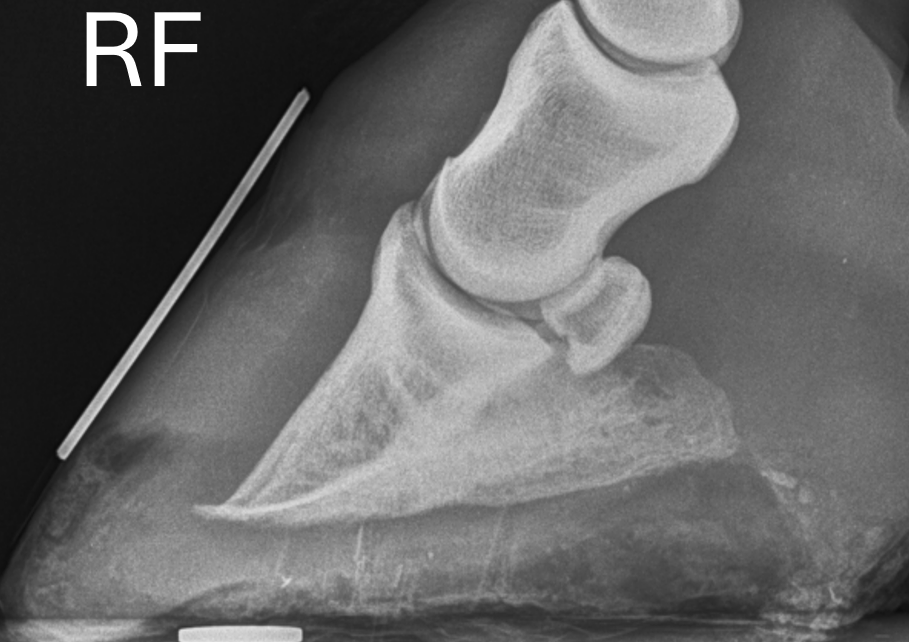

what is this the typical presentation of?

EMS

does this horse have laminitis, if so how can you tell?

Yes

,

P3

is

dropped